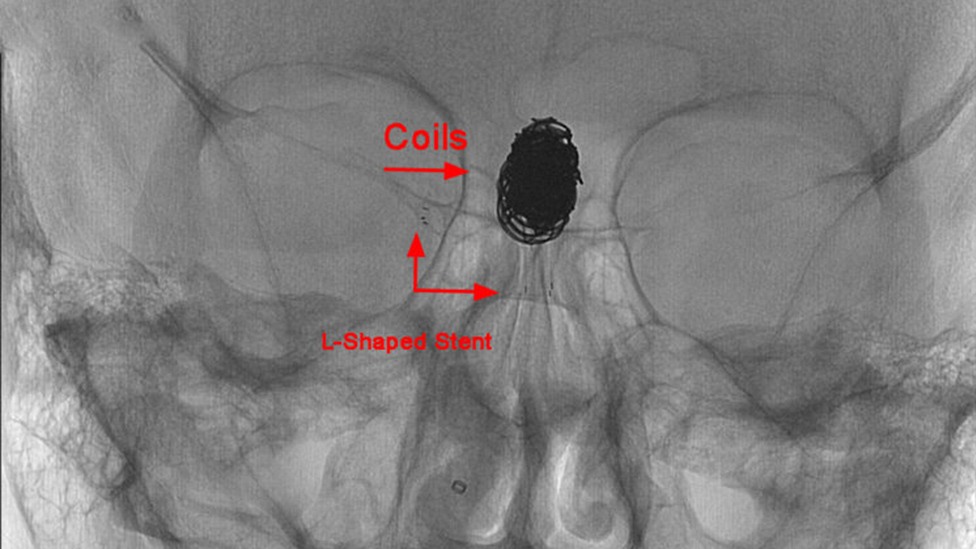

L-Shaped Stent: Before

1 of 3

Neurovascular stents are intended to treat wide-neck, intracranial, saccular aneurysms. Pictured, l-shaped stent: Before

L-Shaped Stent

2 of 3

L-Shaped Stent: After

3 of 3